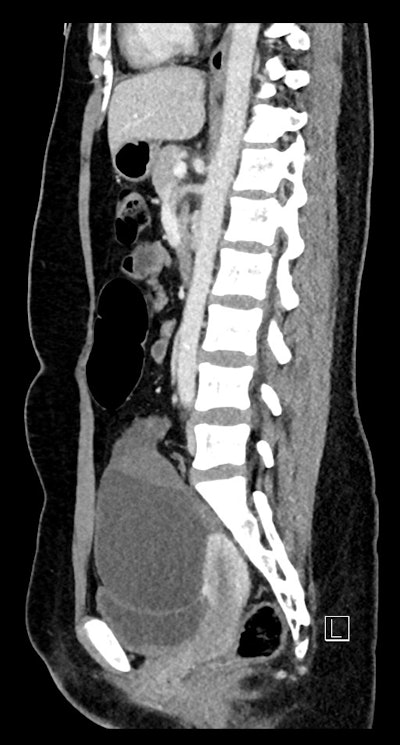

CT sagittal; 25-year-old woman -- the cystic mass is causing mass effect on the urinary bladder and uterus. The left ovary is displaced posteriorly behind the mass (not imaged on this slice).

One patient, a 25-year-old woman, presented with right-sided tenderness and pain with nausea and vomiting over two days. She was afebrile, hemodynamically stable, and her lab markers were within normal ranges. The other patient, a 37-year-old woman, was also hemodynamically stable and afebrile; her tenderness and pain were left-sided and had persisted for four days.

Large ovarian cystic masses were present in both cases; the authors underscored that these are a known risk factor for ovarian torsion, and thus an important finding for diagnosis.